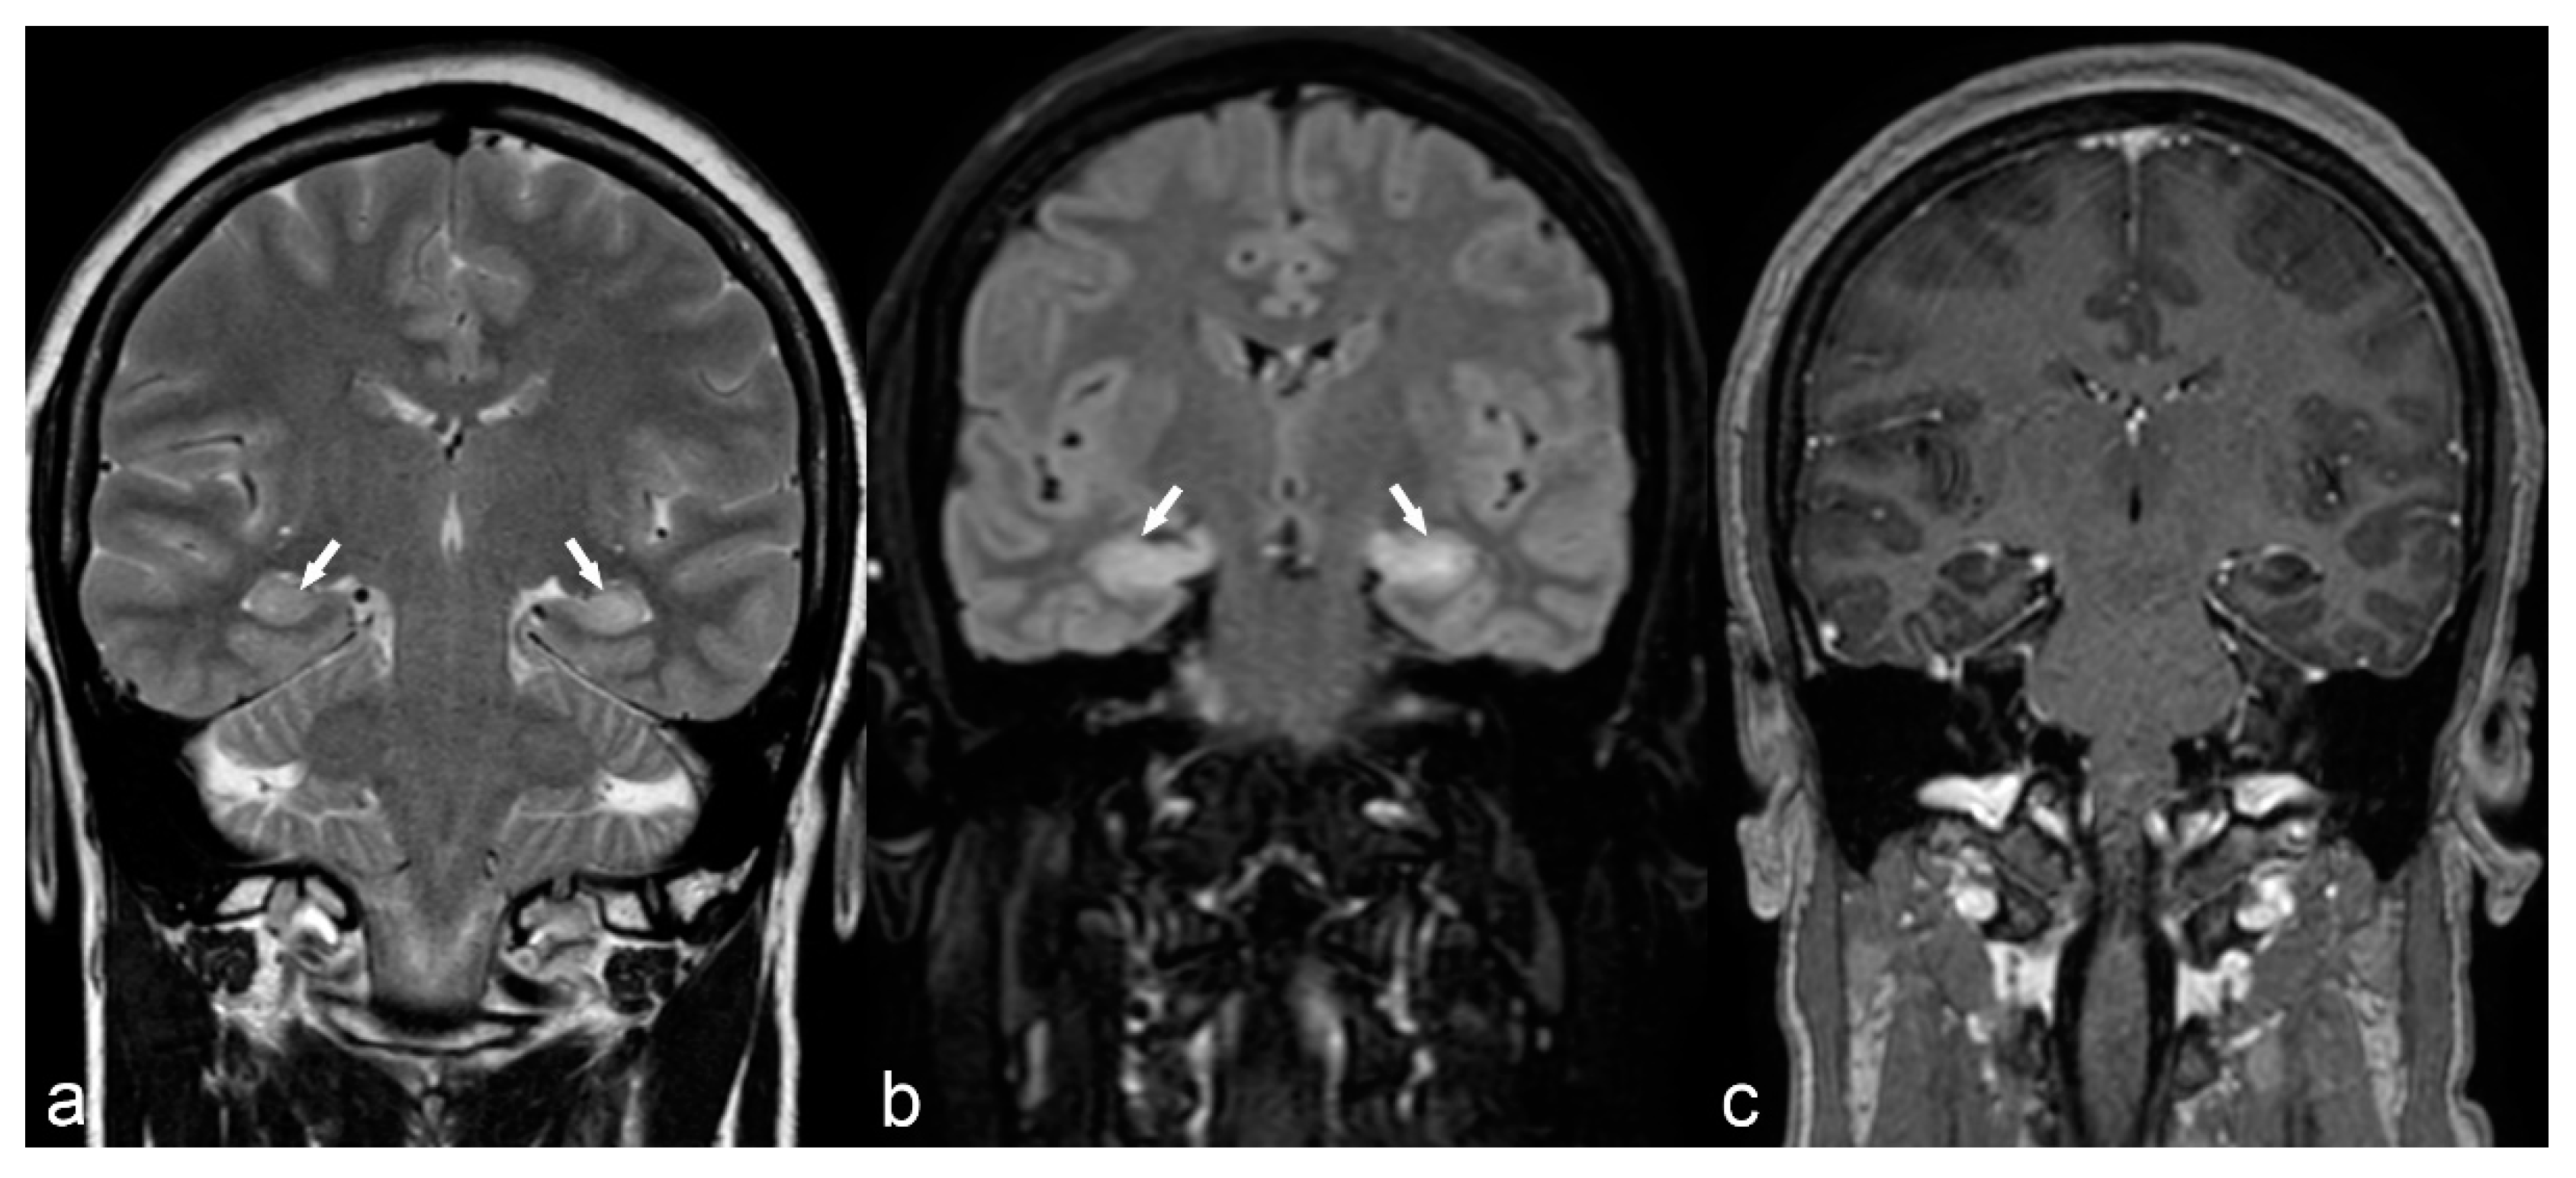

Figure 12.

18-year-old female with medically refractory epilepsy. Coronal T2 (a) and FLAIR (b) images show hemispherical parenchymal volume loss and cortical thinning (asterisk) on the left side with resultant ex vacuo dilatation of the frontal (arrow) and temporal horns (arrowhead) of the left lateral ventricle, consistent with Rasmussen’s encephalitis.

Auto-immune encephalitis is a less frequent cause of epilepsy characterized by high T2/FLAIR signal of the temporal lobe (including the hippocampus), insula and cingulum, usually with bilateral symmetrical or asymmetrical involvement (Figure 13).

Figure 13.

50-year-old woman. Symmetrical hyperintensity is identified on coronal T2WI (a) and FLAIR (b) in both hippocampi (arrows). No abnormal enhancement is seen on 3D T1 Gd (c). This is a case of autoimmune limbic encephalitis.